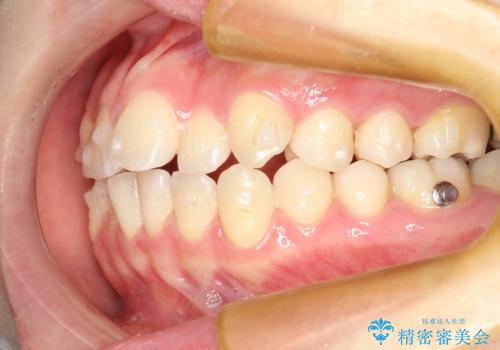

インビザラインによるガタつきの矯正治療 シンプル・短期間

- 20代女性

- invisalign full

- 1年6ヶ月

- 非抜歯、IPR+拡大によるマウスピース矯正を計画した。